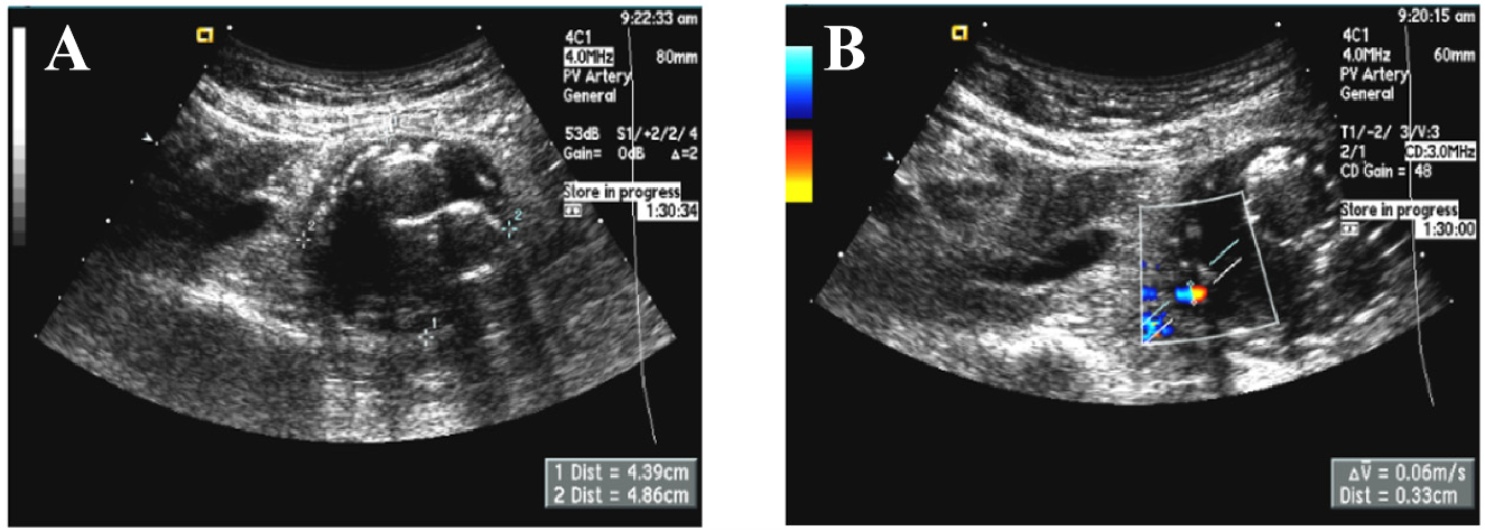

Figure 3. (A) Echocardiography reveals an endovascular aortic stent, with the maximum diameter of the aortic sac measuring 4.86 cm. (B) On color Doppler flow imaging, an endoleak originating from a patent lumbar artery with a diameter of 0.33 cm is visualized, which is located at the left inferior margin of the aneurysm sac

3. (A) 超声心动图显示一个主动脉内支架,其主动脉囊最大直径为4.86厘米。(B) 在彩色多普勒血流成像中,可见来自一条直径为0.33厘米的开放腰动脉的内漏,位于动脉瘤囊的左下边缘